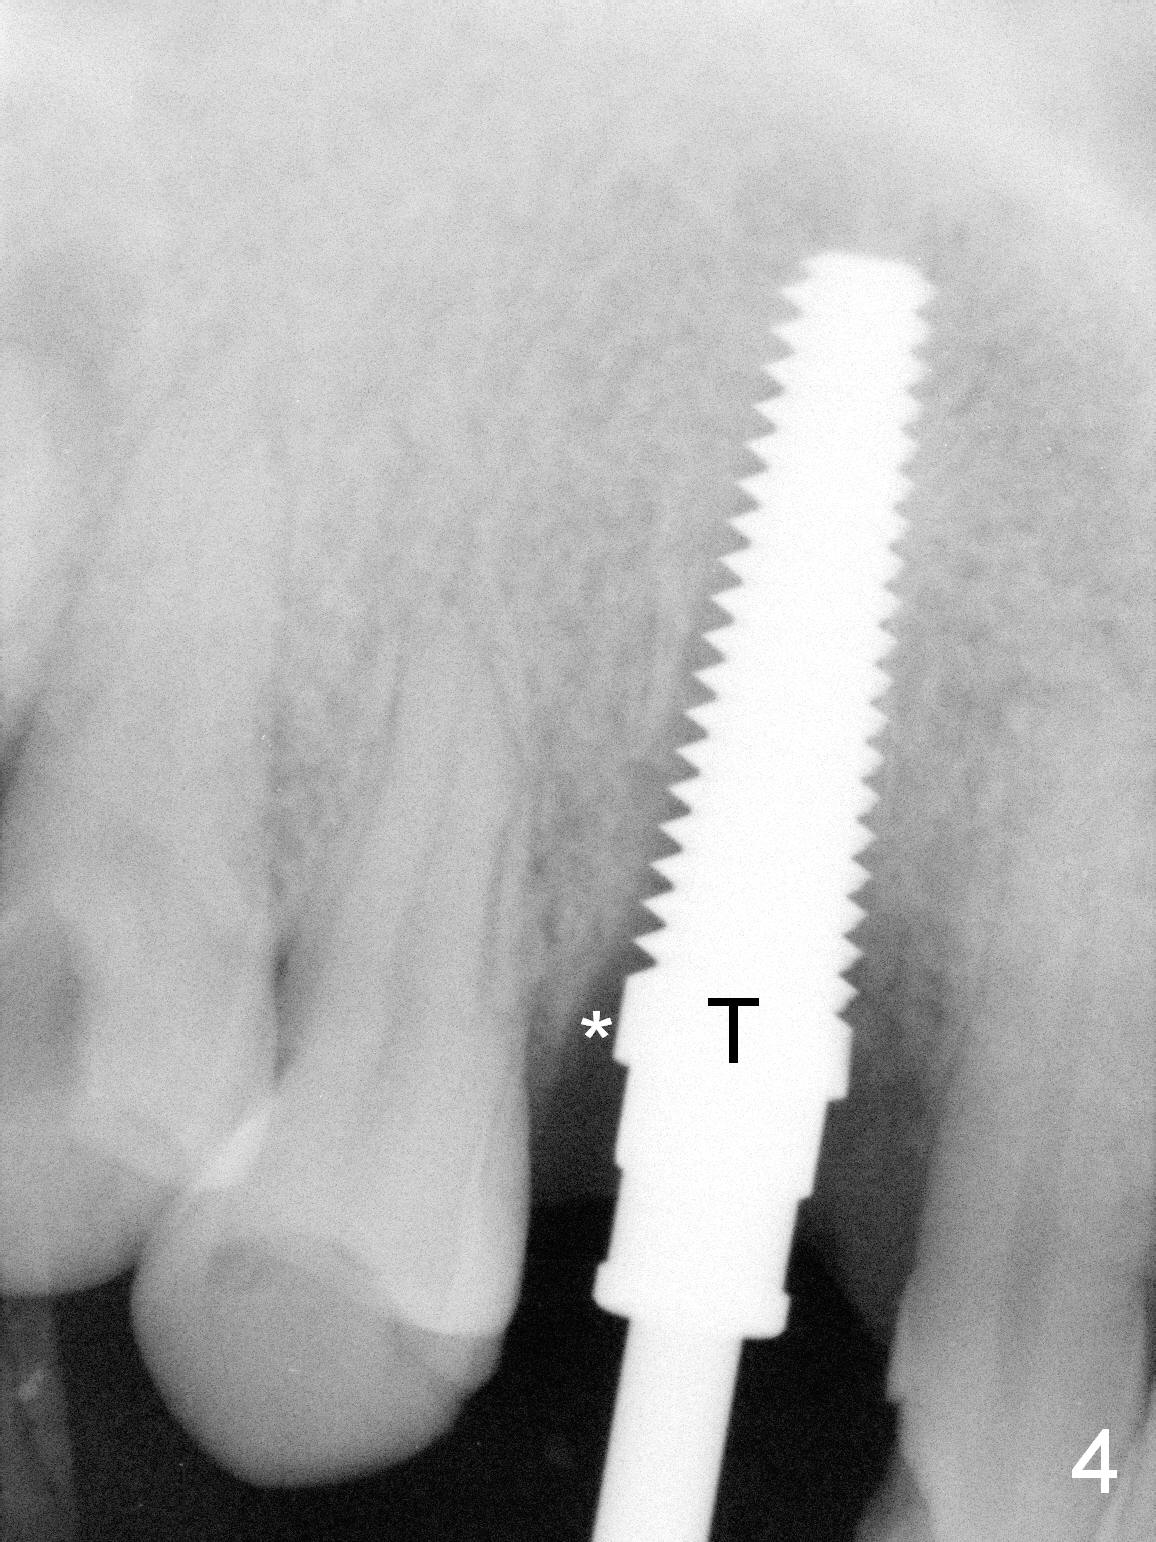

Lengthwise, a longer osteotomy is needed (Fig.4): 20 mm at the gingival level, 17 mm at the bone level. Distal to the 5 mm tap is a gap (*). Initially a shorter osteotomy (by 3 mm) is made: there is minimal engagement with the labial bone (Fig.4' between arrowheads (CT coronal section from not the same patient)). The osteotomy is extended (Fig.4''). This is the second problem to be solved.